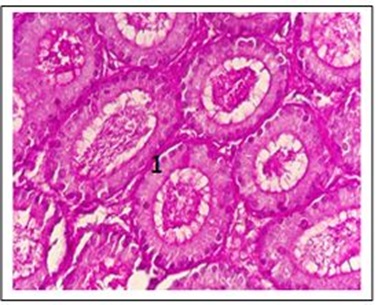

The testis

The testis' basement membrane's contact with PAS was weak, according to the findings of the study in the control group's second week of testis. As displayed in Figure 1, the interaction was moderate in the testis sections of the amitriptyline and escitalopram group (see Figures 2 and 3).

According to the testis for the control group, the testis basement membrane's interaction with PAS was weak as of the fourth week. Figure 4 shows a moderate interaction between amitriptyline and escitalopram in testis sections from that group (see Figures 5 and 6).

A weak contact between the testis' basement membrane and PAS was visible in the control group's testis at the end of the sixth week. Amitriptyline and escitalopram revealed a substantial interaction in the testis sections in Figure 7, 8 and 9.

Figure 1: Two-week examination of the testes of control male mice shows (1) basement membrane reaction with PAS weak

Figure 2: Two-week examination of the testes of amitriptyline male mice shows (1) basement membrane reaction with PAS moderate

Figure 3: Two-week examination of the testes of escitalopram male mice shows (1) basement membrane reaction with PAS moderate (400x)

Figure 4: Four-week examination of the testes of control male mice shows (1) basement membrane reaction with PAS weak

Figure 5: Four-week examination of the testes of amitriptyline male mice shows (1) basement membrane reaction with PAS moderate

Figure 6: Four-week examination of the testes of escitalopram male mice shows (1) basement membrane reaction with PAS moderate

Figure 7: Six-week examination of the testes of control male mice shows (1) basement membrane reaction with PAS weak

Figure 8: Six-week examination of the testes of amitriptyline male mice shows (1) basement membrane reaction with PAS strong

Figure 9: Six-week examination of the testes of escitalopram male mice shows (1) basement membrane reaction with PAS strong